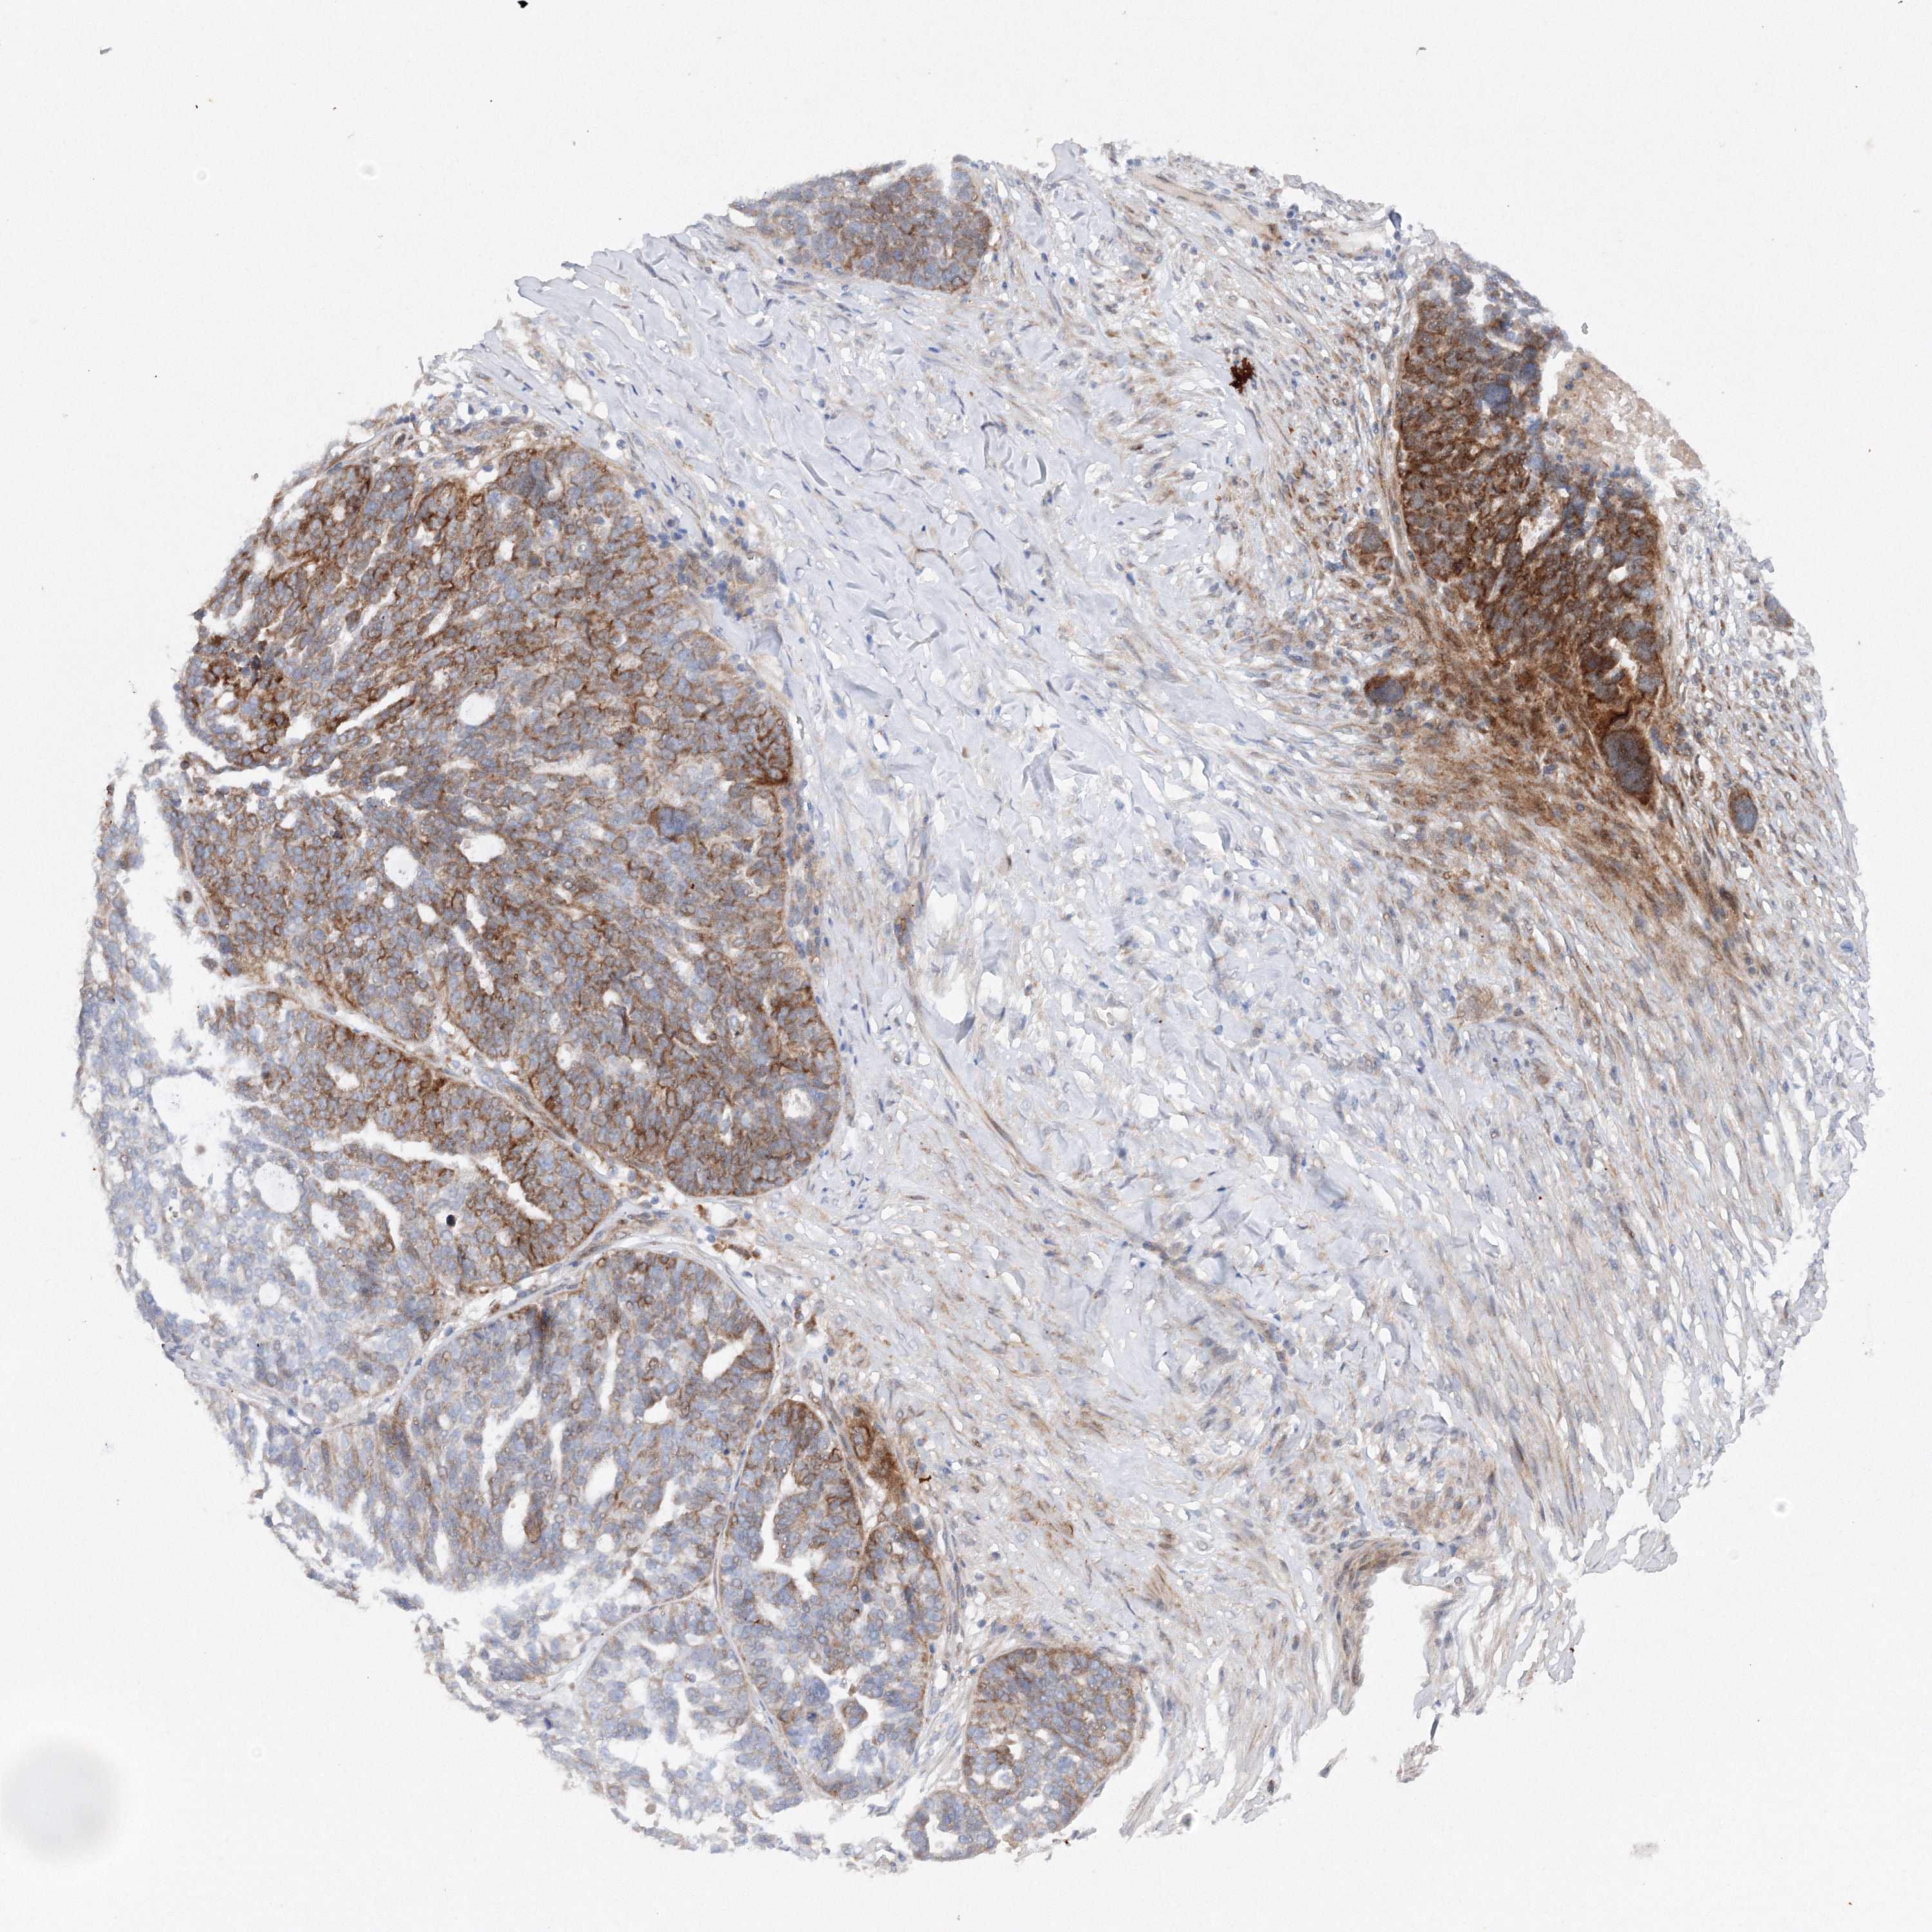

OVARIAN CANCER - Protein expressioni

A mouse-over function shows sample information and annotation data. Click on an image to view it in a full screen mode. Samples can be filtered based on level of antibody staining by selecting one or several of the following categories: high, medium, low and not detected. The assay and annotation is described here.

Note that samples used for immunohistochemistry by the Human Protein Atlas do not correspond to samples in the TCGA dataset.

Antibody stainingi

Antibody staining in the annotated cell types in the current human tissue is reported as not detected, low, medium, or high, based on conventional immunohistochemistry profiling in selected tissues. This score is based on the combination of the staining intensity and fraction of stained cells.

Each image is clickable and will lead to virtual microscopy that enables deeper exploration of all samples and also displays staining intensity scores, fraction scores and subcellular localization as well as patient and tissue information for each sample.

Antibody HPA035937

Staining

High

Medium

Low

Not detected

Intensity

Strong

Moderate

Weak

Negative

Quantity

>75%

75%-25%

<25%

None

Location

Nuclear

Cytoplasmic/membranous

Cytoplasmic/membranous,nuclear

Cystadenocarcinoma, serous, NOS

Carcinoma, endometroid

Cystadenocarcinoma, mucinous, NOS

Carcinoma, NOS